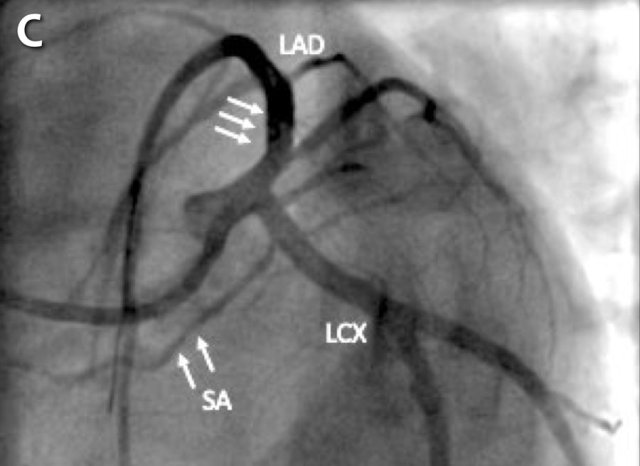

The findings are:

- Moderate (50-69%) stenosis in the proximal LAD caused by a non-calcified plaque.

- Variant of sinoatrial (SA) nodal artery. The artery usually arises from the RCA as a second branch after the conus artery, however in this case it arises from the LCX, courses behind the aorta, anastomosing with the right atrium and with a small branch supplies the SA-node of the heart.

- Thrombus in the apex of the left ventricle.

- CTP was performed in this patient. CTP showed a perfusion defect at stress imaging in the territory of the LAD (I+), at rest no perfusion defect was visible.

This patient classifies as CAD-RADS 3/P1/I+, which means

this patient requires further investigation.

Same patient.

A: Curved MPR of the LAD with non-calcified plaque causing moderate (50-69%) stenosis.

B: The so-called “spider-view” (LAO caudal) of the heart with a 70% stenosis in the proximal LAD. Note the presence of SA nodal artery arising from the proximal LCX and coursing to posterior direction.

C: A drug eluting stent (DES) was implanted into the proximal LAD with good results.